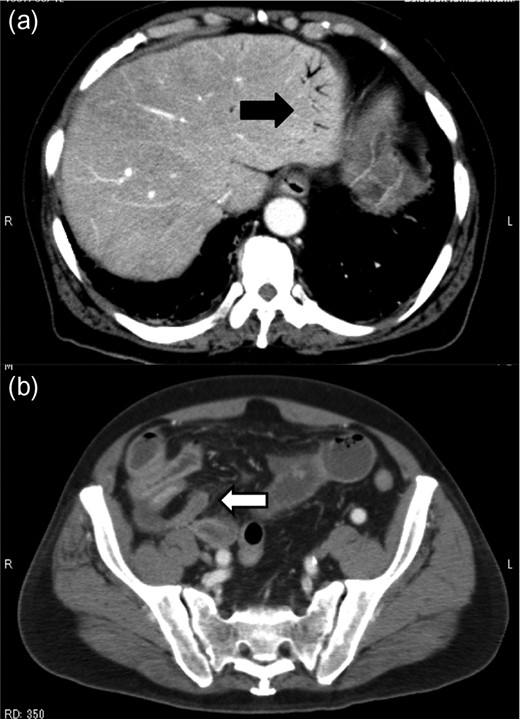

A 79-year-old man with acute abdominal pain had gone to a nearby hospital. As HPVG was detected by abdominal computed tomography (CT), he was transferred to our hospital for further examination and treatment. He had no remarkable past medical history. When he arrived at our hospital, his vital signs were relatively stable (body temperature: 37.2°C; blood pressure: 112/74 mmHg; pulse rate: 68 beats/min). However, physical examination revealed abdominal distention, rebound tenderness and abdominal guarding as signs of peritoneal irritation. The laboratory findings indicated acute inflammation (white blood cell count of 18 400/μL and Creactive protein concentration of 17.7 mg/dL), dehydration and metabolic acidosis (a level of base excess of −7.0 mmol/L). Creatine kinase was remarkably elevated (28 327 IU/L) (Table 1). Plain abdominal radiographs showed distention of the small intestine and suggested subileus (Fig. 1). Contrast-enhanced abdominal CT revealed HPVG (Fig. 2a), a contrast defect in a region of the small intestine, and a small amount of ascites around the intestine. There was no thrombus in any artery; however, the wall of the appendix was moderately thickened when we reevaluated the images retrospectively (Fig. 2b). We performed an urgent laparotomy with the diagnosis of generalized peritonitis caused by intestinal necrosis. A small amount of turbid ascites and a dilated small intestine were observed in the peritoneal cavity. Although the entirety of the small intestine and colon were explored, no intestinal ischemia was detected. Then, we found discoloration of the appendix with wall thickening. We thus made a clinical diagnosis of peritonitis caused by gangrenous appendicitis. Although the appendix wall was fragile, no macroscopic perforation of it was observed. We performed appendectomy and abdominal drainage. Based on the pathological findings, the patient was diagnosed with gangrenous appendicitis, with no evidence of malignancy (Fig. 3). Escherichia coli was positive in the ascitic culture. After the surgery, intravenous antibiotic treatment (meropenem) was administered. The patient subsequently went into septic shock with disseminated intravascular coagulation (DIC). He was therefore admitted to the intensive care unit (ICU), where he received blood purification therapy. The CT images on Day 7 after the surgery showed that HPVG had disappeared (Fig. 4). He left the ICU 7 days after the surgery and was discharged from the hospital another 10 days later.

Abdominal CT on Day 7 after the surgery showed that HPVG had disappeared.